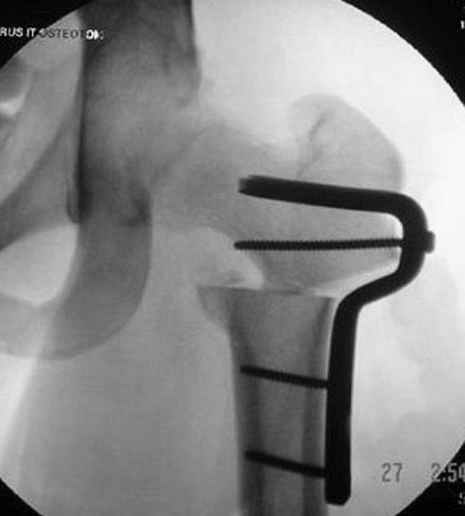

Интраоперционные N5 косая запирательная и N6 подвздошный снимок

11:50 больной в послеоперационной, рентгенограмма N7, компьютерная томограмма в тот же день N8-10

7:30 начало операции, больной на спине, попытка репозиции после анестезии N3, укладка больного на боку, доступ Kocher- Langenbeck, состояние седалищнего нерва около 2.5см кровоподтек, через joistick головка бедра приподнята, освобовождение сустава, фрагмент заднего края более 3х4 см репонирован на свое место. После промывания

сустава, репозиция вывиха (N4), фиксация фрагмента 2.7(4) мм шурупами и допольнительно реконструктивной пластиной на 8 дырок, фиксация 3.5мм шурупами проксимально и дистально.